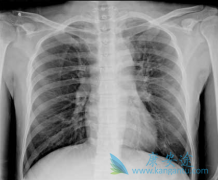

• 早期非小细胞肺癌治疗延迟手术预后差

早期非小细胞肺癌治疗延迟手术预后差

目前,随着影像检查技术的进步,肺部结节检出率日益增多,其中包括许多早期肺癌患者。I 期 非小细胞肺癌 手术疗效很好,甚至可治愈。然而,部分患者由于焦虑等其他原因推迟手术时间。为了明确 I 期非小细胞肺癌推迟手术时间是否影响总体预后,鉴于此来自 ...